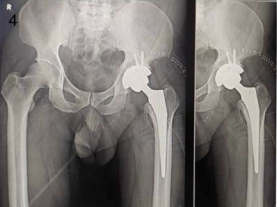

Interestingly, AVN of the hip was more frequently observed on the right side (50%) compared to the left (41.67%) and bilateral presentation (8.33%) among patients with a history of COVID-19. Figures 1 and 2 describe Plain X-rays of pelvis with both hip joints of a 51 year old male and a 43 year old male, having stage 4 AVN of hip, involving the right and left sides respectively. Figures 3 and 4 represent the post-operative X-rays of the above mentioned patients after uncemented THR on the respective sides.

Figure 3: Post-operative X-ray of right hip AVN after uncemented THR on right side.

Figure 4: Post-operative X-ray of left hip AVN after uncemented THR on left side.

Figure 3

Figure 4